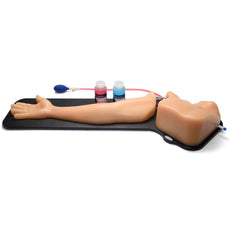

These bone-fracture training blocks help learners develop and practice the psychomotor skills necessary to gain ultrasound proficiency, including using ultrasound system controls, positioning and moving the transducer, recognizing bone fractures and manipulating fractured bones to identify normal versus abnormal imaging characteristics. Choose from two options: Greenstick Fracture, or Crepitus Fracture.

RESPECTIVE ANATOMY:Crepitus Bone Fracture

Greenstick Bone Fracture